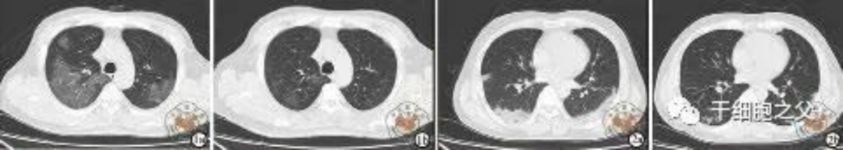

與安慰劑組相比,人臍帶間充質(zhì)干細胞修復組全肺病變體積改善了10.8%,并且人臍帶間充質(zhì)干細胞修復組在每一個隨訪節(jié)點都顯示出固體組分病變體積比例減少。此外,人臍帶間充質(zhì)干細胞組有17.9%的患者在12個月時CT圖像變?yōu)檎#参縿┙M沒有。

研究結(jié)果:細胞輸注后,炎癥指標改善,復查胸部CT提示雙肺病灶較前吸收,呼吸道癥狀改善,新型冠狀病毒核酸檢測連續(xù)2次陰性,治愈出院。